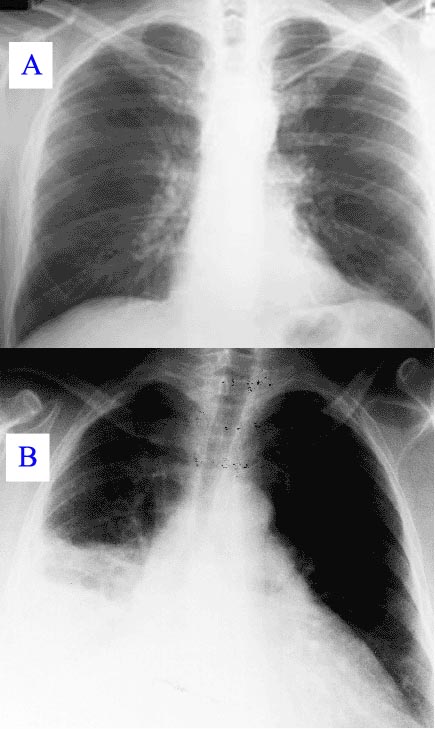

Tudnivalók a tüdőgyulladásról

A tüdőgyulladásoknak, ha nem kezeltetjük időben, számos szövődménye kialakulhat, sőt vannak esetek, amikor halállal végződik. Kialakulhat tüdőtályog, vagy másodlagosan mellhártyagyulladás, melynek következtében a mellhártya üregében folyadék szaporodhat fel, ami légzési nehézséget okozhat a betegeknek.